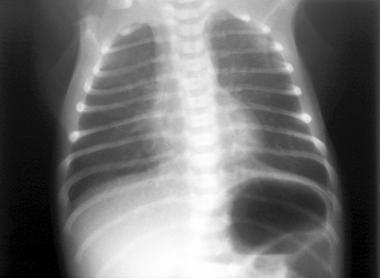

A 3-day-old term male infant is brought to the ED by EMS after being seen at their Family Physician’s office with a low temperature (33.1oC). The child has been feeding poorly for about 12 hours, and has vomited twice. He is lethargic on examination and poorly perfused with intermittent apneas lasting ~ 20 seconds. He requires immediate fluid resuscitation and broad-spectrum antibiotics. His perfusion will improve after IVF boluses, however the apneas will persist and necessitate intubation.

Initial CXR for the case found here:

(CXR source: http://emedicine.medscape.com/article/414608-overview)

Post-intubation CXR for the case found here:

(CXR source: https://radiopaedia.org/articles/neonatal-pneumonia)